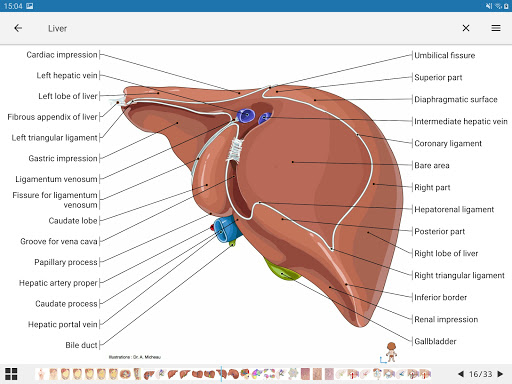

* تحسين عرض التفاصيل للأجزاء التشريحية لتسهيل التعرف عليها في صور الوحدات الحالية والوحدات الأخرى.